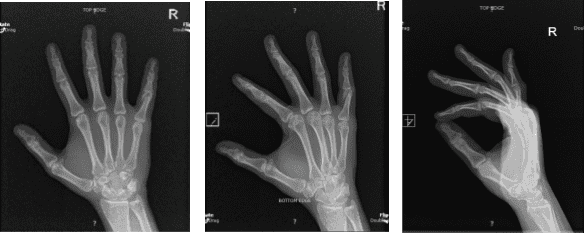

X-ray Right hand minimum 3 years